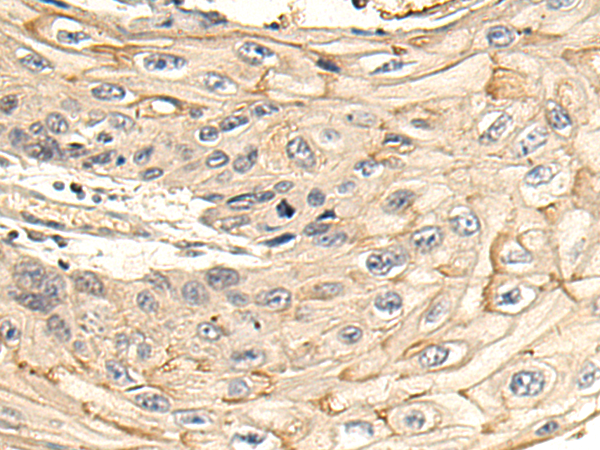

IHC positive control:

human lymphoma tissue and human tonsil tissue

IHC Recommend dilution:

30-150